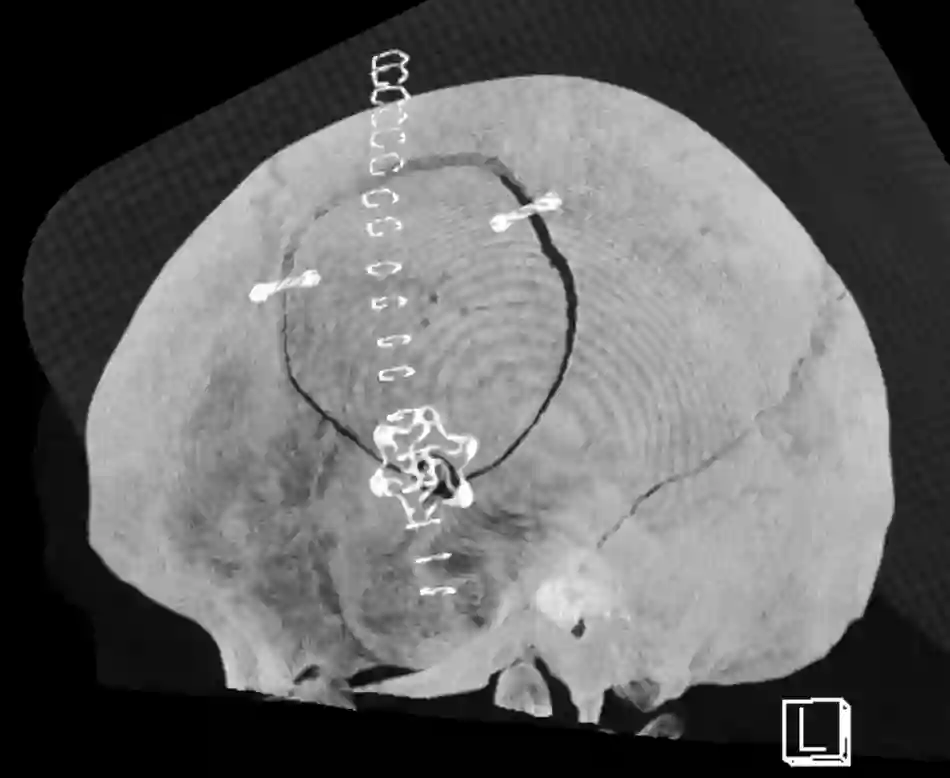

Osteoplastische Kraniotomie

Darstellung einer osteoplastischen Kraniotomie in einem CT. Die Befestigung des Knochendeckels erfolgte bei diesem Patienten mit Titanplättchen.